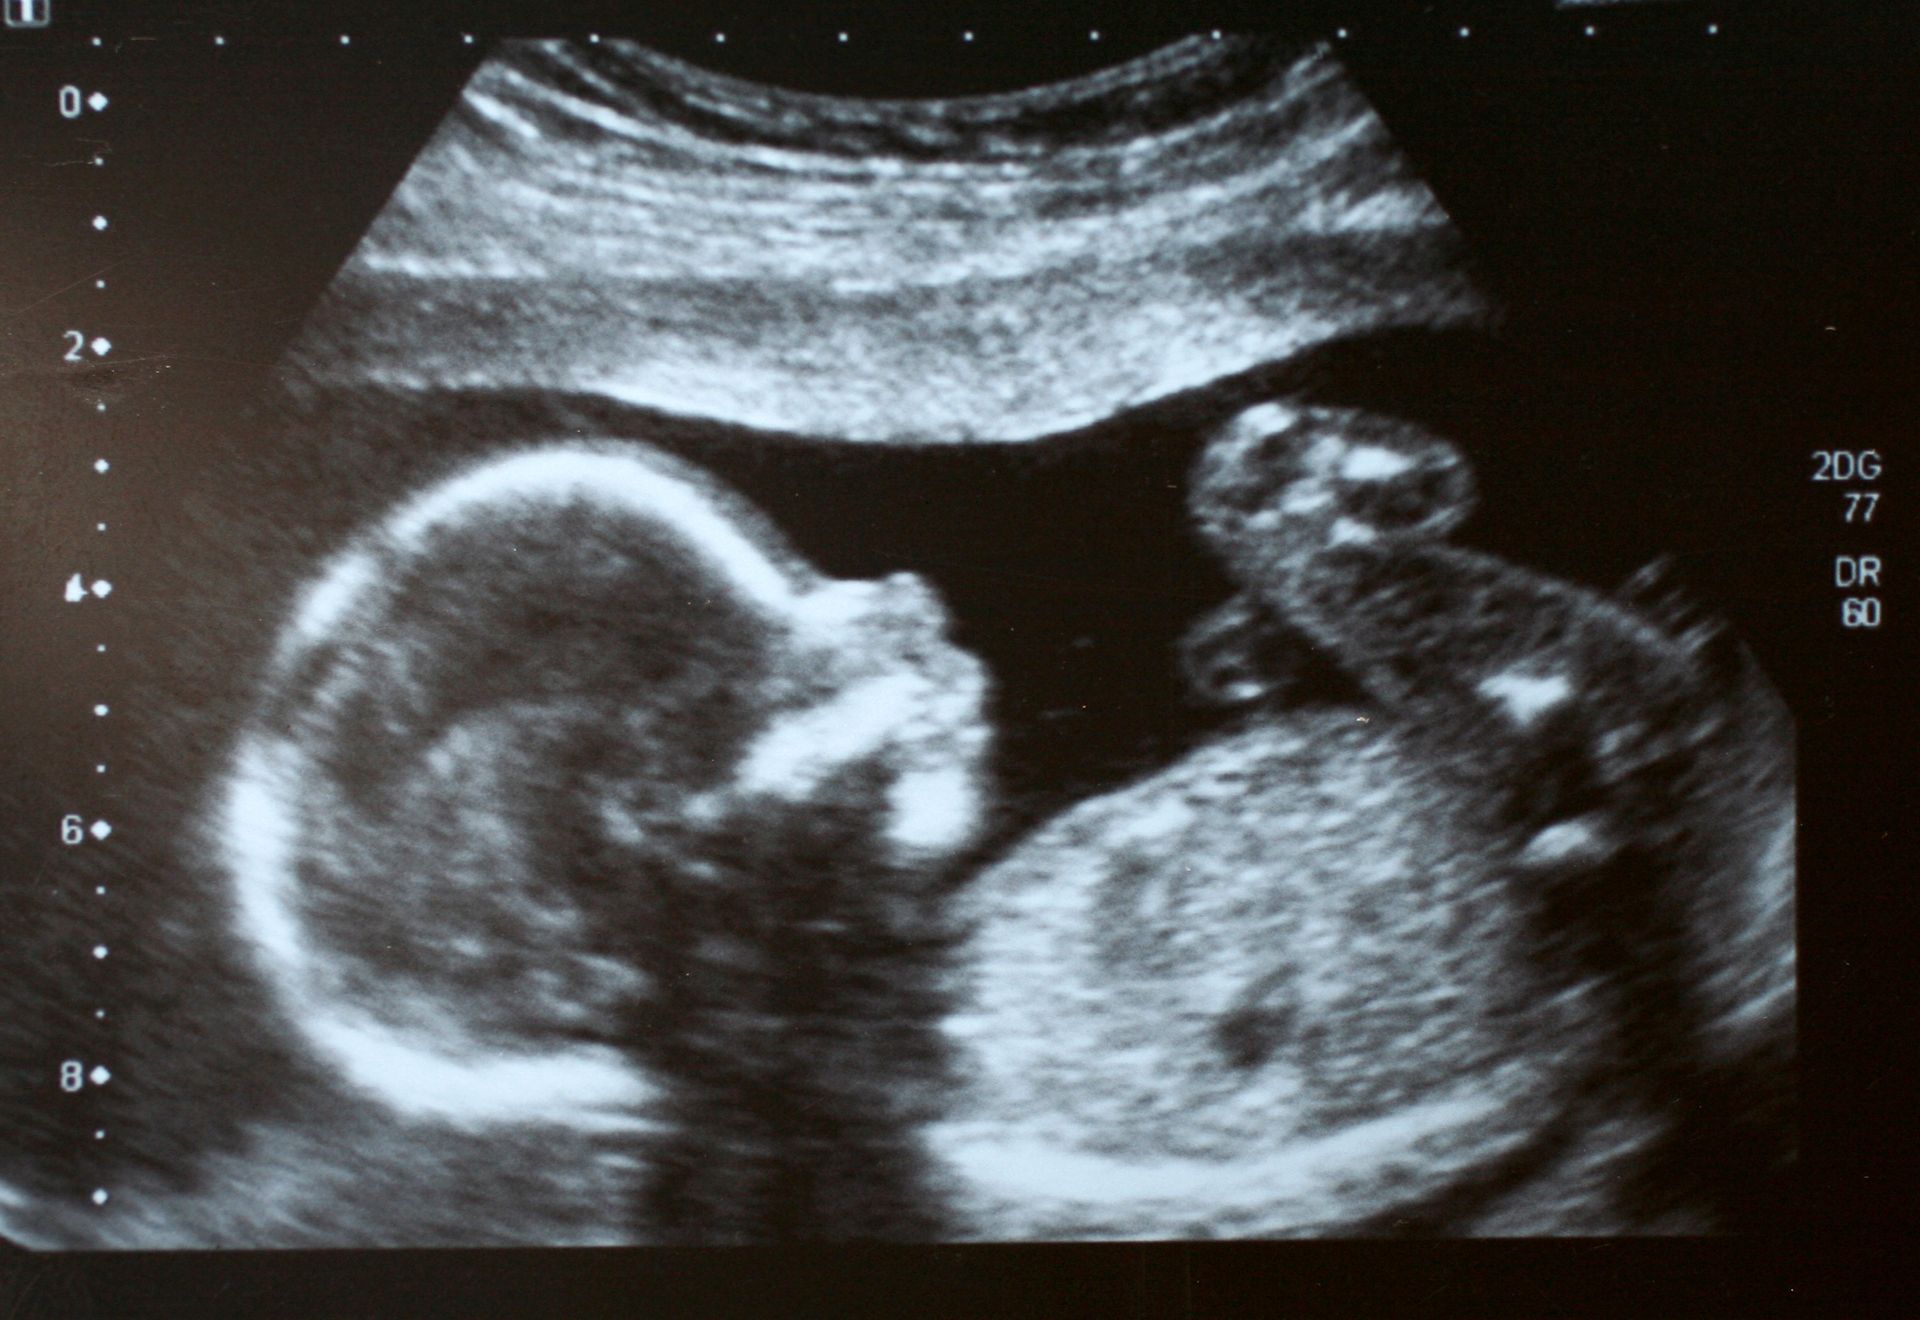

Il dottor Gianni Pirisi è un medico chirurgo specializzato in ostetricia e ginecologia, specialista in diagnostica ecografica prenatale ed ecografie 3D e 4D.

Lo studio che presiede è specializzato nella diagnostica prenatale ed è dotato delle più moderne apparecchiature, al fine di espletare con maggiore professionalità prestazioni mediche relative all'ecografia endovaginale, l'amniocentesi, l'ecografia 3D e 4D, ecografia ostetrica-ginecologica e diagnostica ecografica prenatale.